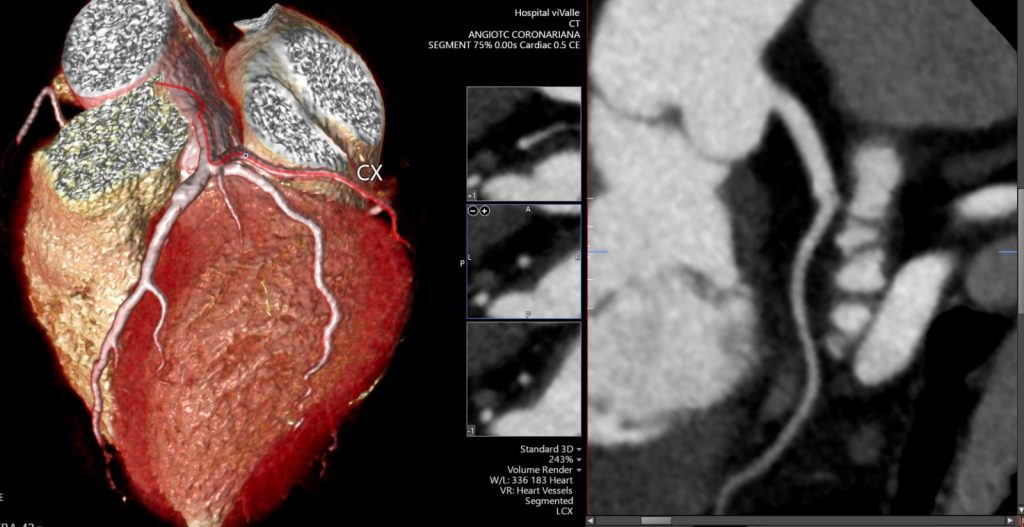

A angioTC de coronárias (CCTA) vem ganhando protagonismo na prevenção primária porque vai além do escore de cálcio: ela identifica placas não calcificadas, muitas vezes invisíveis ao CAC, e que podem representar aterosclerose ativa e risco real mesmo em pessoas classificadas como “baixo risco” pelos escores tradicionais.

Um grande estudo populacional recente (JAMA), com quase 25 mil indivíduos de 50 a 64 anos sem doença cardiovascular conhecida e seguimento de aproximadamente 8 anos, mostrou que a presença de placa não calcificada na CCTA se associou a maior risco de primeiro evento coronário e que a inclusão dessas informações anatômicas melhorou a predição de risco e a reclassificação, principalmente entre os pacientes inicialmente rotulados como baixo risco.

Na prática, isso muda o jogo: detectar precocemente placas não calcificadas permite “antecipar” o diagnóstico da doença coronária, individualizar a prevenção e orientar medidas mais assertivas — especialmente em pacientes que, pelo cálcio ou pelo risco clínico, poderiam ser falsamente tranquilizados.